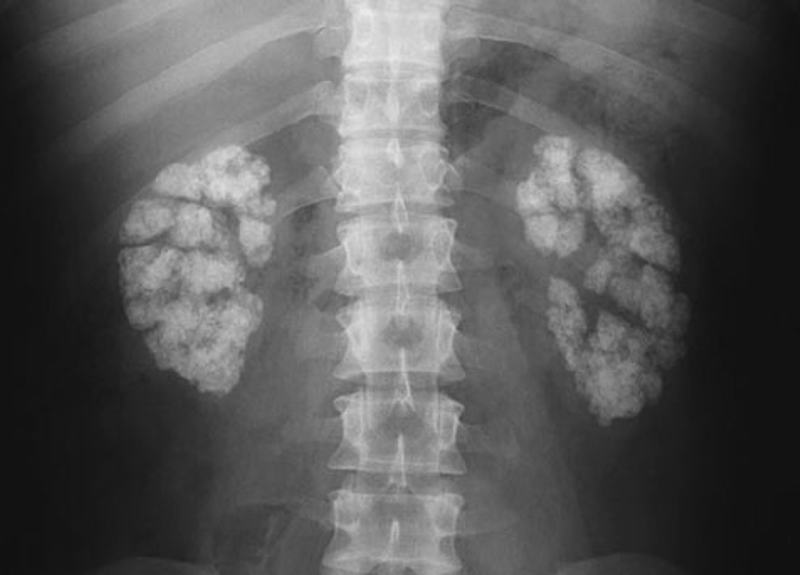

• ↑Ca++ excretion : 2° hyperparathyroidism, nephrocalcinosis, renal stones